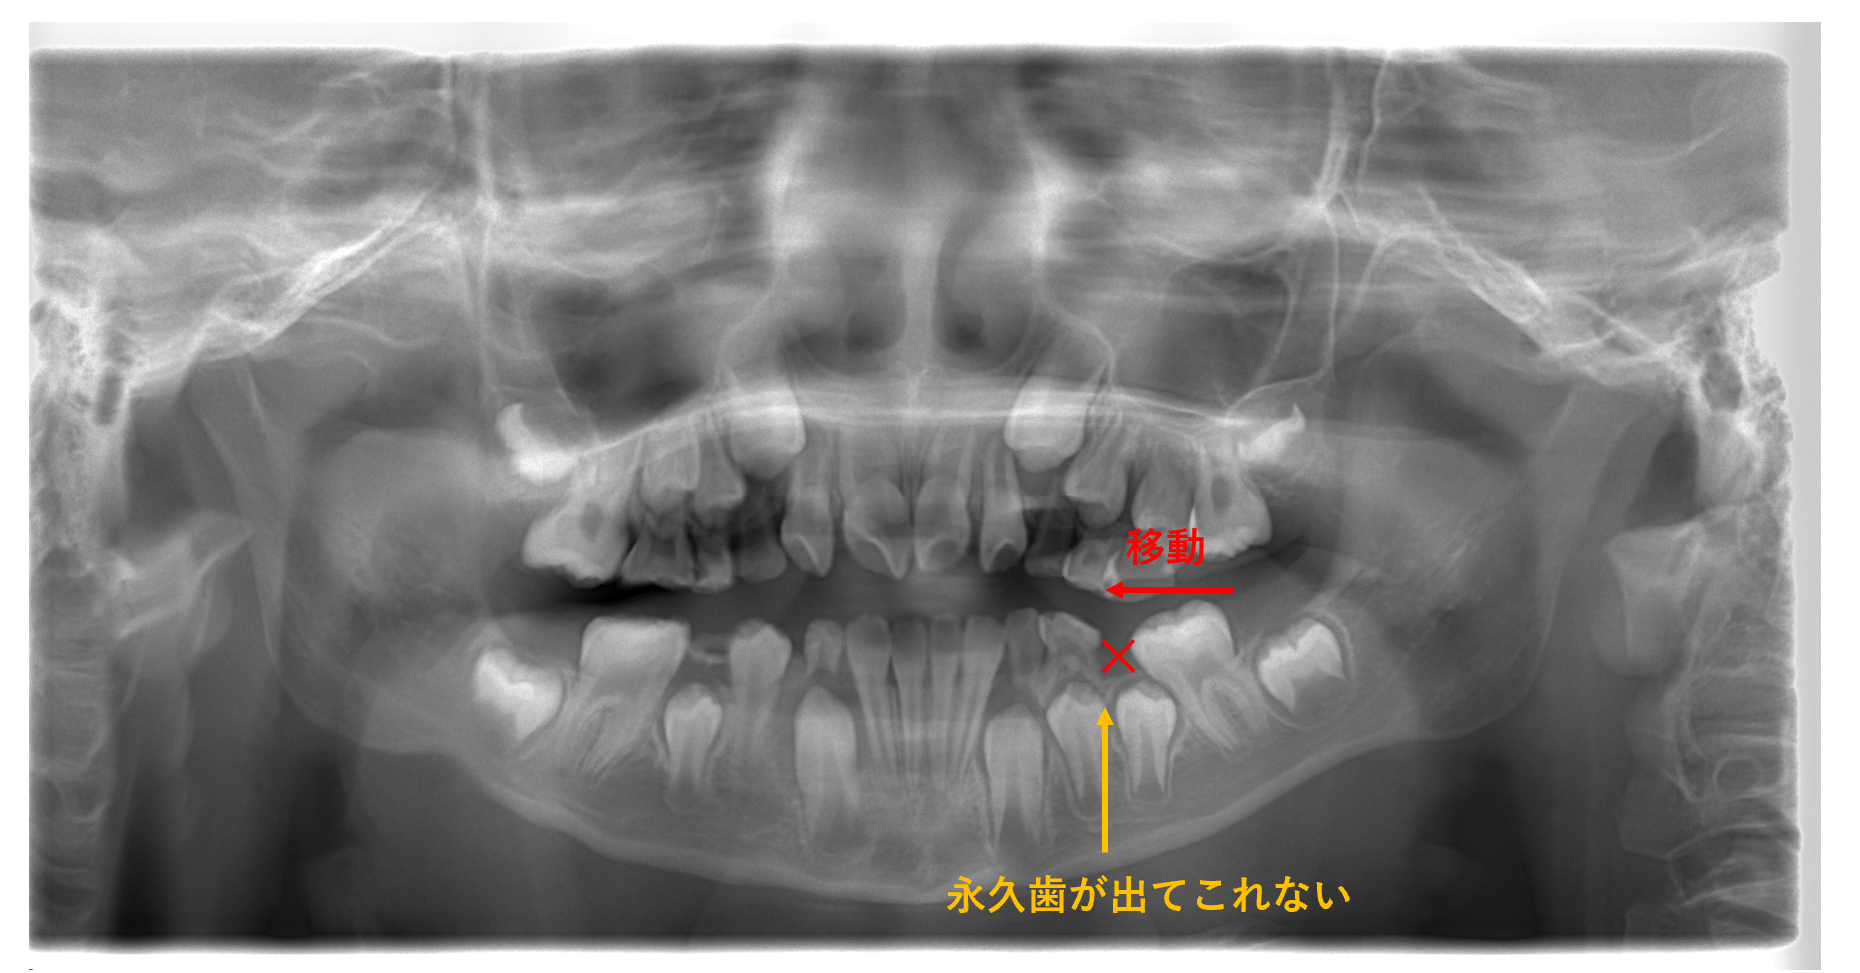

② 歯並びが悪くなる

虫歯で早期に乳歯がなくなってしまった場合、隣の歯が傾いてしまったり

隣の歯が移動してきてしまい、後から生えてくる永久歯の生える隙間が少なくなります

したがって、永久歯が生えてこれなくなってしまったり

正しい場所ではない所から、生えてくる可能性があります

こちらのレントゲンでは、乳歯が早期になくなり

永久歯の6番目が前歯側に寄ってきてしまい

5番目の歯が出てこれない状態です。